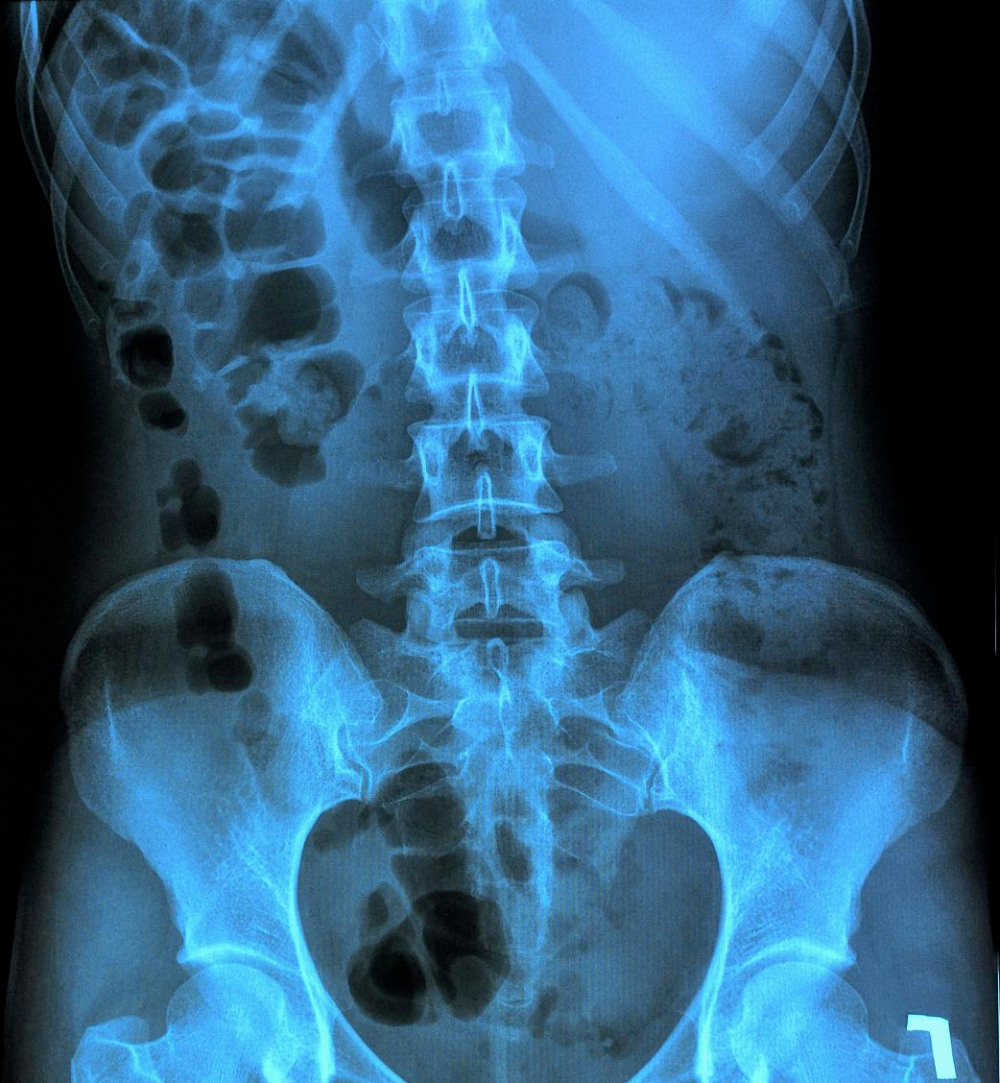

今天来看一位患外周型强直性脊柱炎2年的患者,片子上的情况如何